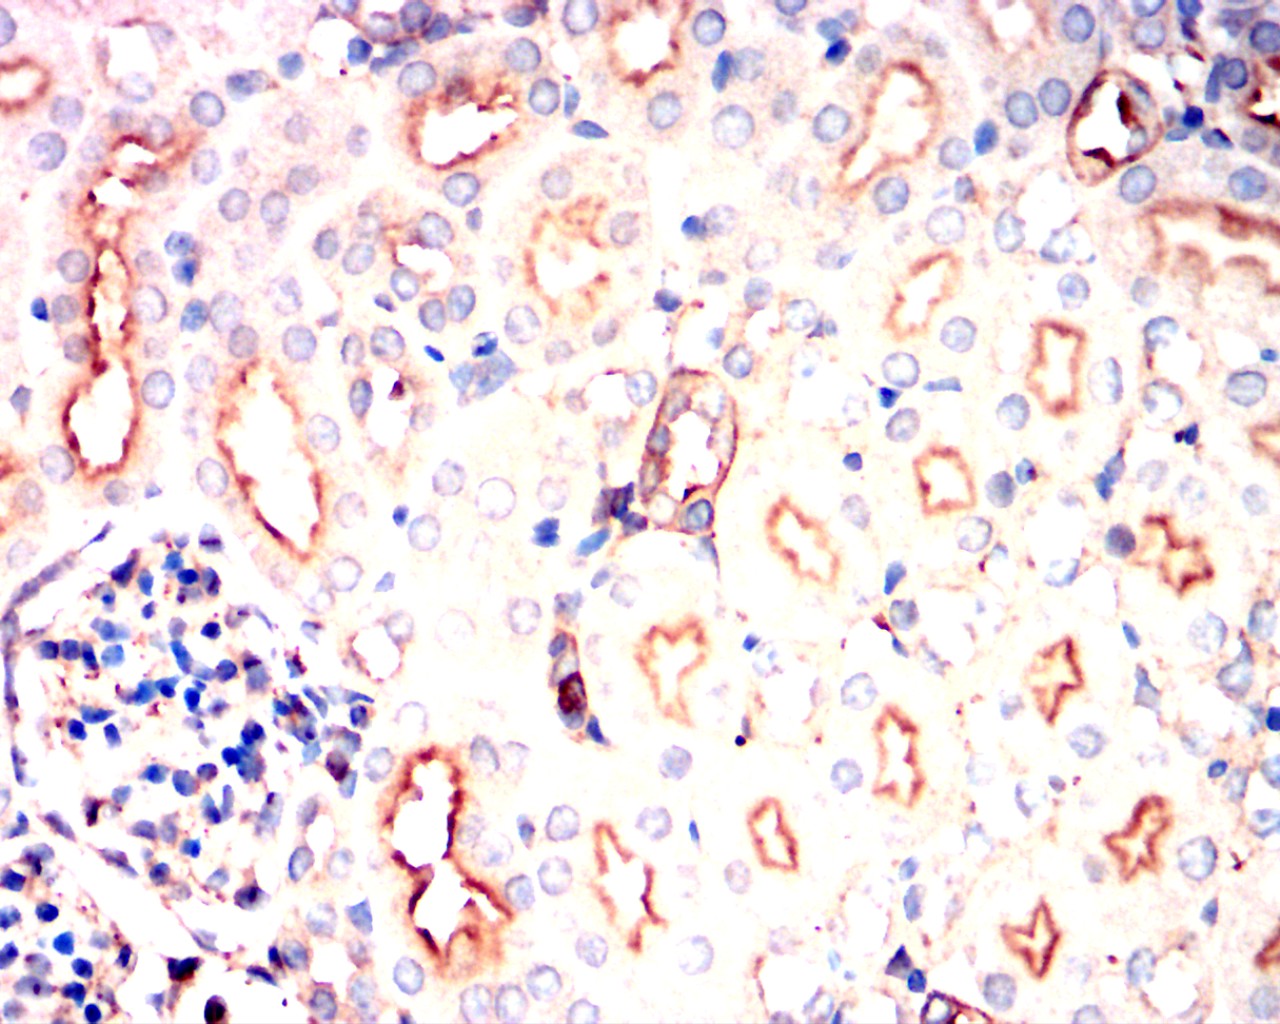

Immunohistochemical analysis of paraffin-embedded mouse kidney showing cytoplasmic localization using PIK3CA mouse mAb with DAB staining.

Immunohistochemical analysis of paraffin-embedded rat kidney showing cytoplasmic localization using PIK3CA mouse mAb with DAB staining.